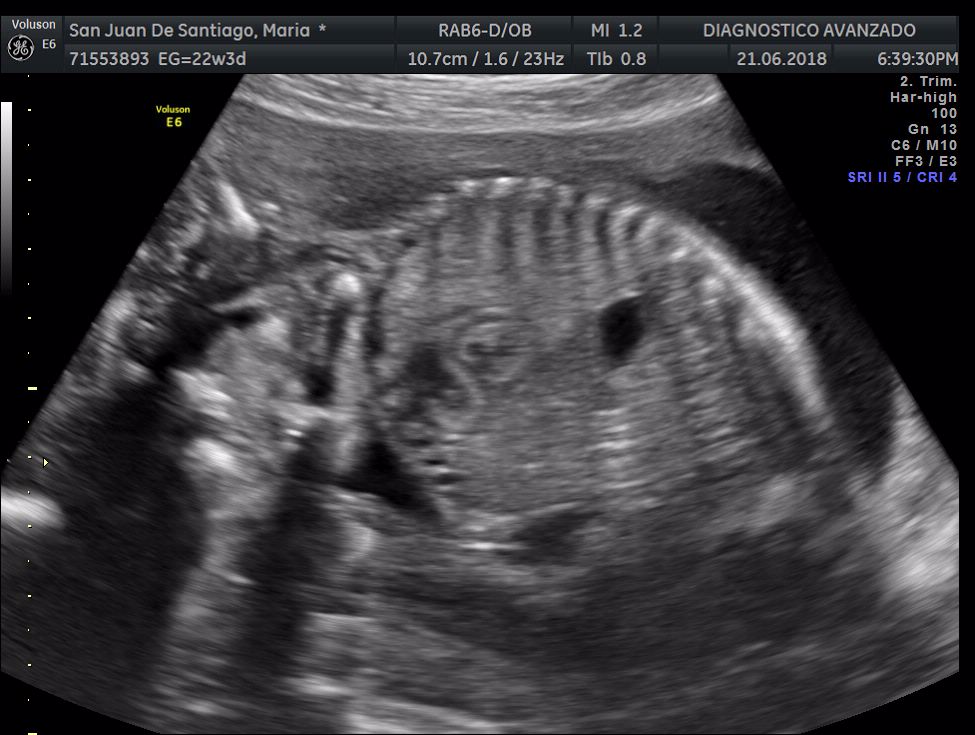

¡Hola a todos! Hoy hemos ido a hacer la tradicional ecografía 3D de la niña, os dejamos todo el material (aunque es un poco demasiado).